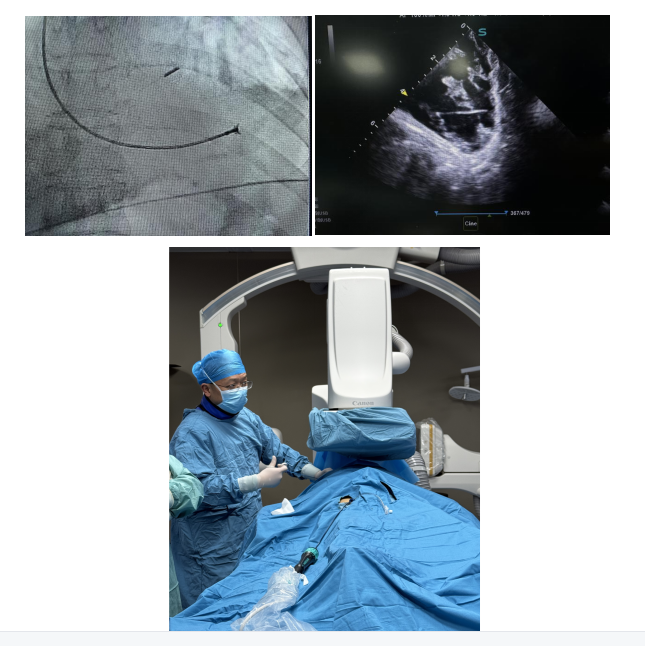

手术团队采用微创经血管心肌活检技术,张翔主治医师及刘志远住院医师顺利完成股静脉及颈内静脉穿刺,建立手术通路,全程监测血流动力学变化。在心腔内超声实时引导下,朱舜明主任操控活检钳精准定位右心室间隔部,共钳取块心肌组织5块用于病理学诊断,最终活检病理结果显示心肌淋巴细胞浸润及坏死灶,证实免疫性心肌炎诊断,排除急性冠脉综合征及其他心肌病可能。依据病理学诊断,联用免疫抑制剂并调整糖皮质激素剂量后,患者病情逐步稳定,目前在康复治疗中,该技术为免疫治疗相关心脏毒性的早期识别提供了“金标准”,避免经验性治疗的盲目性。